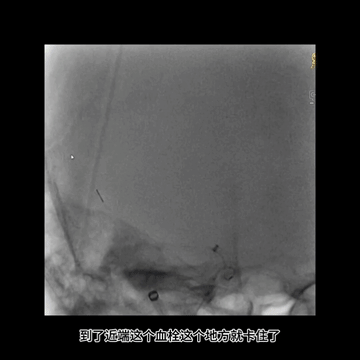

3、第一次抽拉结合取栓,5F中间管无法紧密嵌合血栓,回撤中间管时血栓脱落ICA

其次,这个患者血栓不仅坚韧而且比较大,第一次抽拉结合取栓后,5F中间管头端虽然吸住了血栓,但嵌合不牢固,负压回撤中间管时血栓脱落卡在ICA后交通开口处。此坚韧血栓再次导致微导丝通过困难,微导丝成袢后才最终通过。